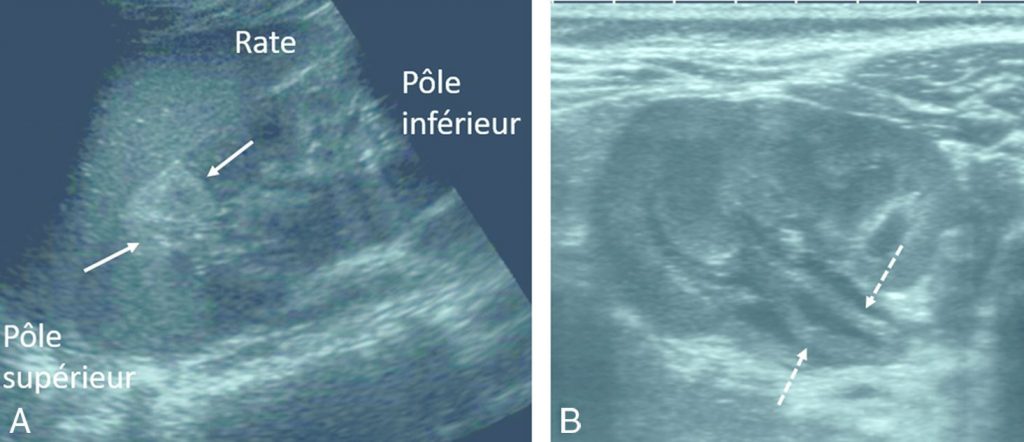

Fig. 106.1 Pyélonéphrite aiguë chez un enfant de 3 ans (A) et chez un nourrisson de 2 mois (B).

Coupe longitudinale du rein gauche mettant en évidence une image triangulaire hyperéchogène du pôle supérieur du rein gauche (flèches) (A). Coupe axiale du rein gauche mettant en évidence un épaississement de la paroi du pelvis rénal (flèches en pointillé) (B).

Source : CERF, CNEBMN, 2022.